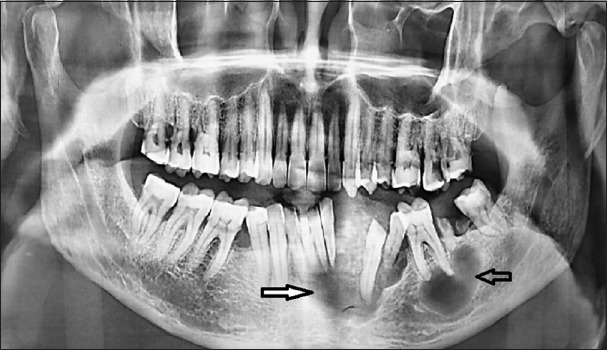

Gingiva is one of the common sites for many reactive, benign and malignant lesions. Localized gingival overgrowths usually present with a wide variety of clinical and histopathological features, and it will create a challenge for proper diagnosis. We report a case of a 48-year-old male patient with a slow-growing swelling on the lower anterior gingiva, extending to the floor of the mouth. A differential diagnosis of pyogenic granuloma or salivary gland neoplasm was considered. The lesion was diagnosed as clear cell variant of calcifying epithelial odontogenic tumour after the histopathological and immunohistochemical evaluation of multiple biopsy specimens from different sites of the lesion. Clear cell variant of calcifying epithelial odontogenic tumour is a very rare, aggressive variant of CEOT which demands proper clinicopathologic and radiographic examination for diagnosis. It also highlights the necessity for multiple biopsies in case of larger gingival lesions.